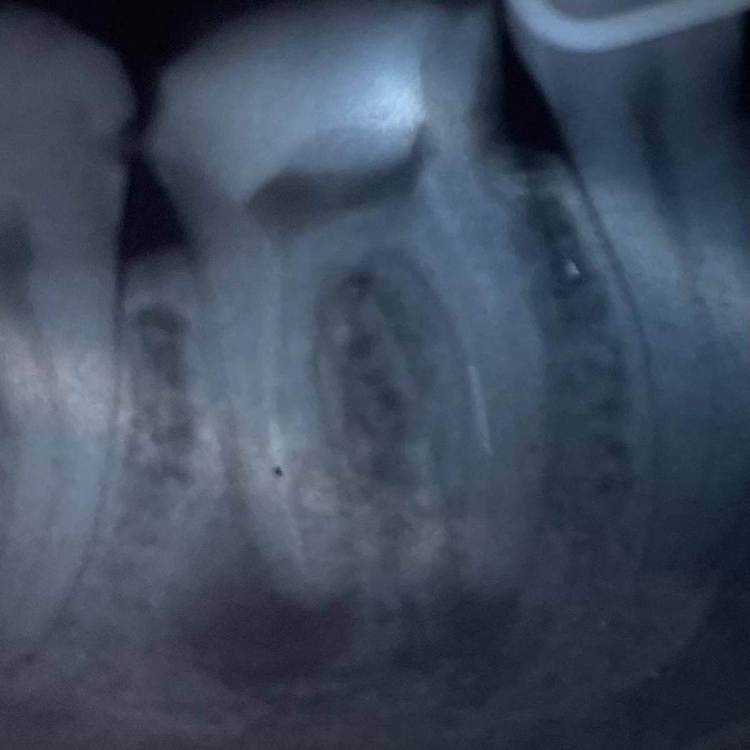

1586Doc Опубликовано 17 мая, 2021 Автор Поделиться Опубликовано 17 мая, 2021 ретрит 46 зуб. Извлечение фрактуры. Дальше будет вкладка и ожидание )) 2 Ссылка на комментарий

Александр23712 Опубликовано 21 сентября, 2021 Поделиться Опубликовано 21 сентября, 2021 (изменено) @1586Doc Фрактура - это трещина. Поэтому "Извлечение фрактуры" немножко режет глаз. *не с целью оскорбить, просто поправка. А работа хорошая. Обработка профайлы? Гидроокись сразу из канюли не страшно вводить? Изменено 21 сентября, 2021 пользователем Александр23712 Ссылка на комментарий

1586Doc Опубликовано 21 сентября, 2021 Автор Поделиться Опубликовано 21 сентября, 2021 10 часов назад, Александр23712 сказал: @1586Doc Фрактура - это трещина. Поэтому "Извлечение фрактуры" немножко режет глаз. *не с целью оскорбить, просто поправка. А работа хорошая. Обработка профайлы? Гидроокись сразу из канюли не страшно вводить? Фрактура - это надлом, перелом)) с немецкого Fraktur — надлом. Обработка профайлы до 30/06. Пару недель гидроокись, потом вертикальная конденсация. Проблем с выводом гидроокиси из канюли никогда не получал. Ссылка на комментарий